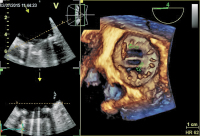

Mitralklappenprothese - Regurgitation

Abbildung 2: Paravalvuläres Leak mit geringfügiger Regurgitation.

Mitralklappenprothese - Chirurgenblick

Abbildung 3: Dreidimensionale Darstellung der Mitralklappenprothese in der sogenannten Chirurgenansicht. Mehrere Vegetationen am Klappenring (Pfeile)